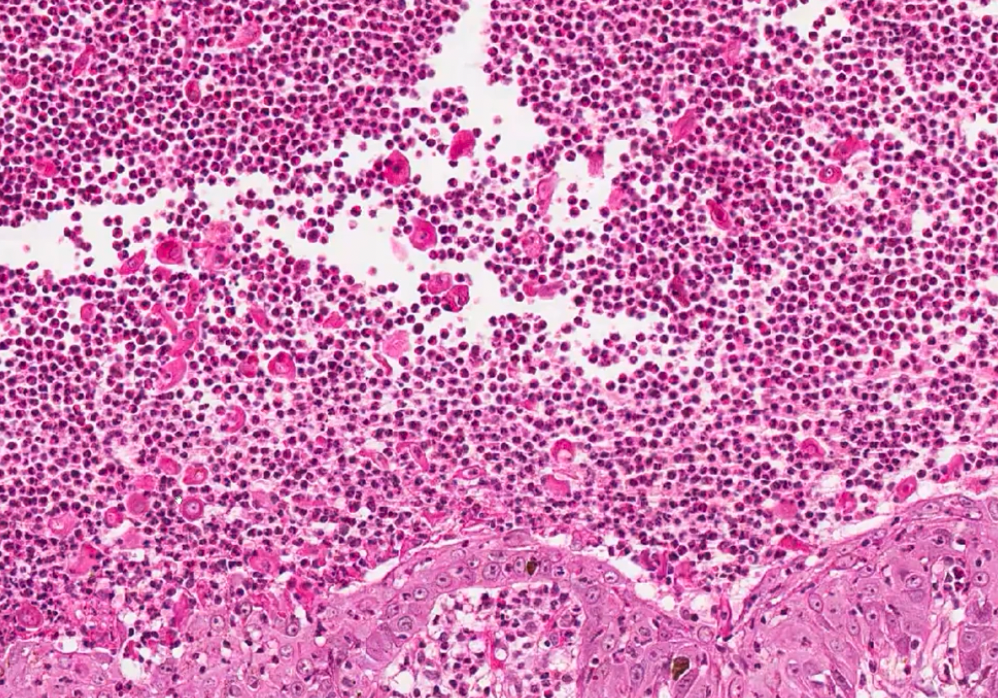

Puggy, 12 yr old MC, Shih tzu, is seen for lameness marked pawpad hyperkeratosis with crusting and erosions. The abdomen is also markedly hyperpigmented. You perform a minimum derm database (skin scrapings, impression smear, etc) and find superficial bacterial infection but you are concerned about a more serious disease. You perform a skin biopsy.

E-slide #5, located in slot 2.

The biopsy report is as follows:

The epidermis is expanded by acanthosis and severe diffuse parakeratotic hyperkeratosis. Multiple zones of pallor (intracellular edema) are located in the spinous layer. The basal layer is marked expanded and irregular. These features create a “red, white and blue” appearance to the epidermis. A neutrophilic pustule is also located in the epidermis. The superficial dermis has a mild perivascular inflammatory infiltrate.

What is your diagnosis?

superficial necrolytic dermatitis